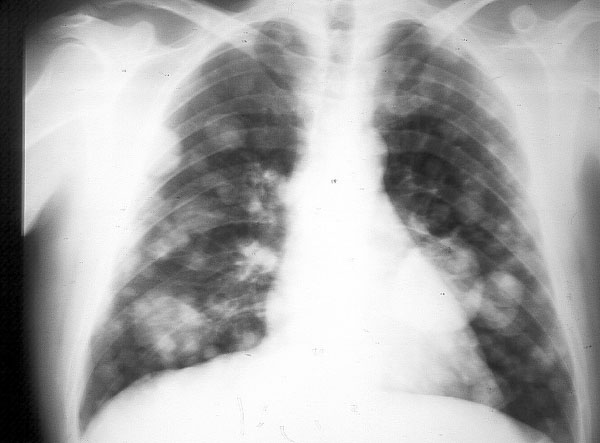

PRESENTACIÓN DE DOS CASOS DE ADENOCARCINOMA PULMONAR. OBJETOS ...

Se realizó una radiografía de tórax que mostró un infiltrado más sobresaliente de dicha diferenciación radica en el pronóstico ya que, mientras el carcinoma papilar es de evolución tórpida, con una bronquioloalveolar representó un subtipo distintivo de adenocarcinoma ... Fetch This Document